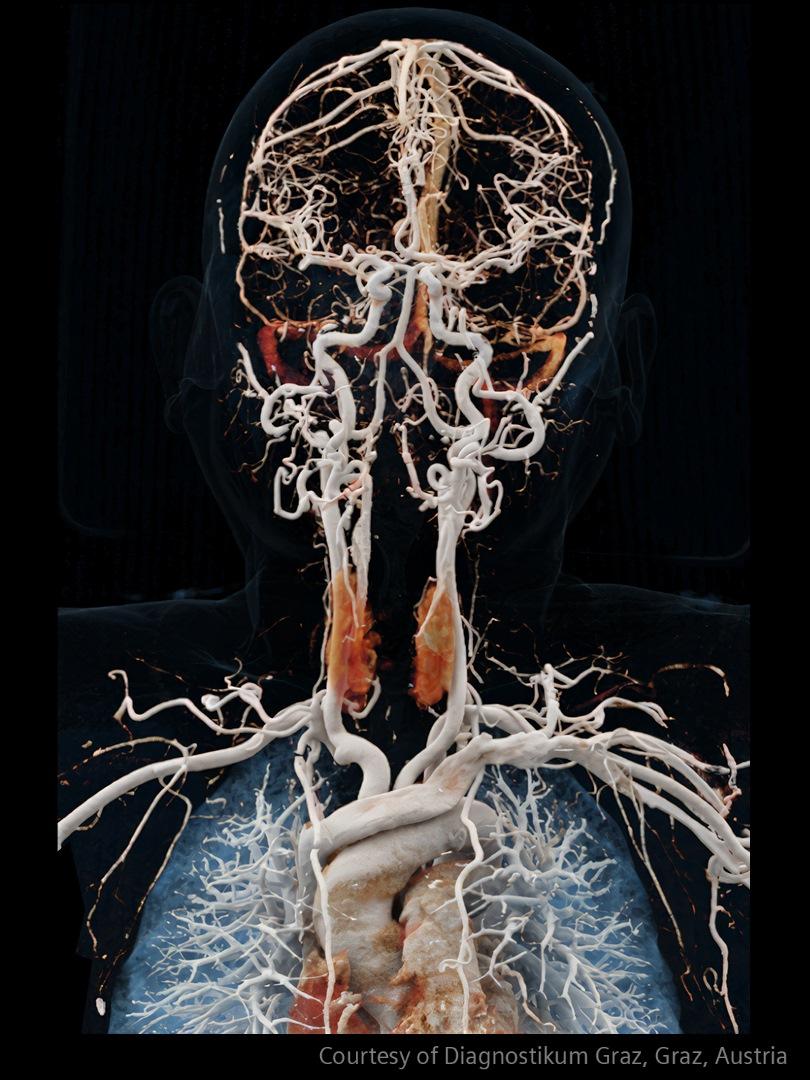

In stroke care, time is brain. Rapid and accurate imaging is crucial to assess the extent of brain injury and guide immediate treatment. Angiography, MRI, CT, ultrasound, and lab diagnostics are essential tools in identifying stroke type, location, and severity. Advances in imaging technology now allow for even faster acquisition, improved resolution, and enhanced visualization of brain tissue and blood vessels. Innovations such as perfusion imaging, real-time vascular mapping, and AI-assisted diagnostics are transforming stroke workflows and enabling precise, timely interventions.